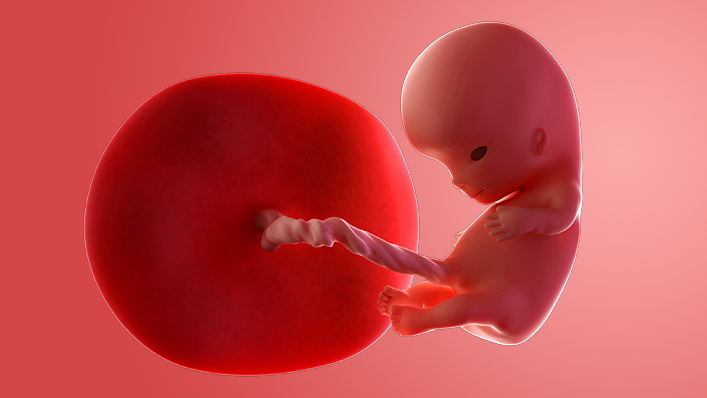

Your baby is now around 16mm long, which is about the size of a raspberry. By next week, they will be twice the size!

The tiny head has started to uncurl a bit. Their arms are getting longer and are bigger than the legs as the upper part of the body grows faster than the lower part. The legs are getting longer too, although the knees, ankles, thighs and toes have not developed yet.

Around now, your embryo becomes a "foetus", which means offspring in Latin.